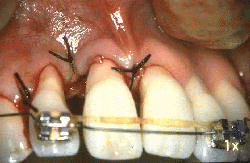

Se realiza las suturas de los colgajos.  Note el cierre completo de los colgajos en interproximal.

El procedimiento de Widman modificado fue realizado y la imagen muestra la apariencia clínica  7 días después del postoperatorio. El paciente se ha enjuagado dos veces por día con  chlorhexidine durante 7 días.